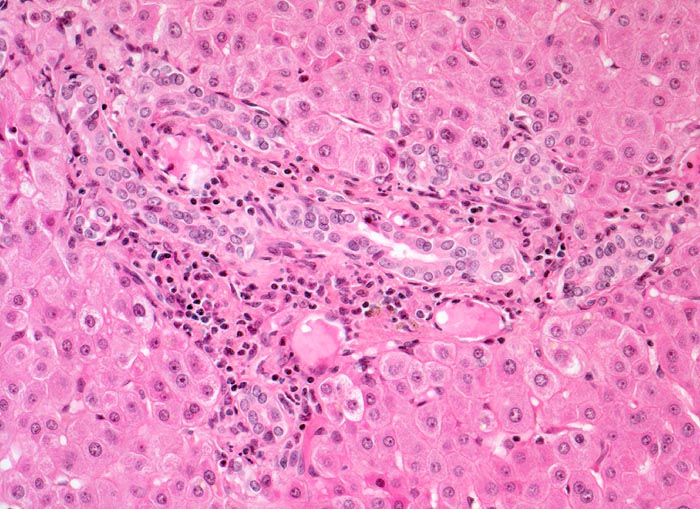

PathoPic – image database / PathoPic ID 4497 - Leber bei mechanischem extrahepatischem Verschlussikterus

Leber bei mechanischem extrahepatischem Verschlussikterus

In der Zone 1 rund um das Portalfeld sind keine Galleablagerungen erkennbar. Das Portalfeld in der Bildmitte zeigt ein gemischtes Entzündungsinfiltrat. Ductulusproliferation am Rand des Portalfeldes.

Differentialdiagnostisch muss im vorliegenden Fall an die Möglichkeit einer medikamentös bedingte Cholestase gedacht werden (Bsp. Antibiotika). Bei einer medikamentös bedingten Cholestase sind die Ductulusproliferationen aber meist deutlich weniger ausgeprägt.